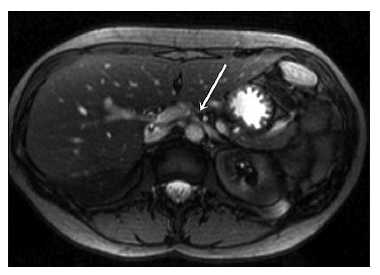

胡桃夹综合征是盆腔静脉淤血综合征的特殊表现形式,由于左肾静脉夹藏于肠系膜上动脉和腹主动脉间,导致左肾静脉狭窄,继而引起左肾静脉周围血管屈曲扩张并导致相关组织器官出现的功能紊乱,表现为血尿、左卵巢静脉血液返流等(图19-5)。胡桃夹综合征的诊断:1、出现血尿相关的症状2、左侧腰痛3、盆腔充血4、盆腔及外阴静脉曲张5、CT、MRI、超声等影像学检查提示存在左肾静脉压迫6、血管造影术证实存在左肾静脉压迫。胡桃夹综合征可以通过不同手术方式进行治疗,包括左肾静脉旁路的建立及自体左肾髂窝移位。但文献报道的手术例数均较少,有效的治疗有待进一步研究。

图19-5 MRI-T2 显示左肾静脉被肠系膜上静脉压迫出现胡桃夹综合征